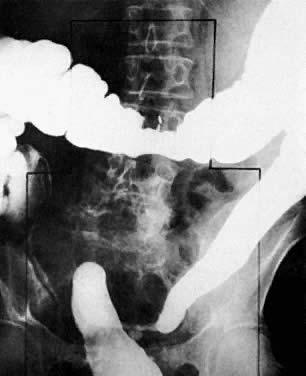

Patients with suspected mechanical bowel obstruction should be examined by a barium enema followed, if necessary, by small-bowel enteroclysis. Besides confirming the presence and site of obstruction (Fig. 42), these studies may show bowel loop displacement (Fig. 43) or may sometimes identify the cause of the obstruction, such as metastatic deposits to the bowel wall (Fig. 44).

Fig. 42. Colon examination shows bowel obstruction ( arrow) in sigmoid colon. Patient has advanced endometrial carcinoma.

Fig. 43. Colon examination shows displacement of the sigmoid colon by a pelvic mass from endometrial carcinoma.

Fig. 44. A 62-year-old woman with cervical cancer. Small-bowel follow-through shows encasement of the distal jejunum ( arrow) causing proximal obstruction.

More recently, CT with opacification of the bowel by diatrizoate sodium diluted to 2% or barium sulfate diluted to 2% was shown to be capable of establishing the presence or absence of small-bowel obstruction. In addition, in most patients, CT has the benefit of determining the cause of obstruction and the presence or absence of metastatic tumor to the small-bowel serosa and mesentery (see Fig. 24D).114,115 Both MRI (see Fig. 19) and CT (see Fig. 24C) may be helpful in detecting local spread to the rectum.